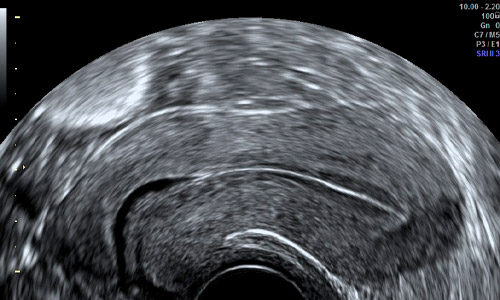

Visión del útero por ecografía